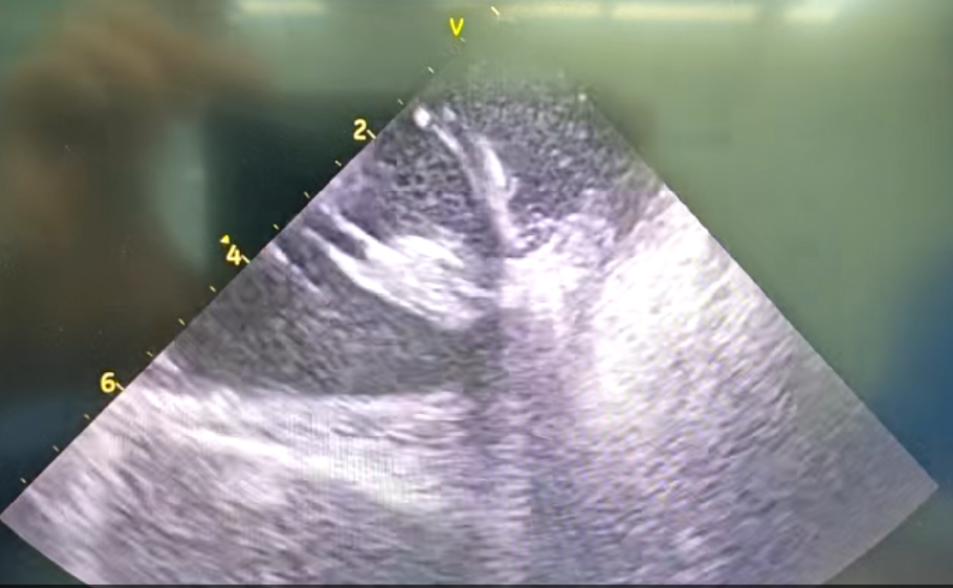

王林林主任医师谨慎操作,成功进入心外膜达到病变位置。术中,患者反复自发多形态室速,且转为室扑,同时出现血流动力学不稳定,需多次电除颤方能终止发作,标测难度极大。这就要求医疗团队必须在有限的标测时间内精准定位室速消融靶点,并结合心内外膜基质特征制定消融策略。经针对性消融后,患者未再自发室速,且室性早搏转为单一形态,经判定为右心室乳头肌来源,随即予以一并消融。术后经心室程序电刺激验证,室速未再被诱发。